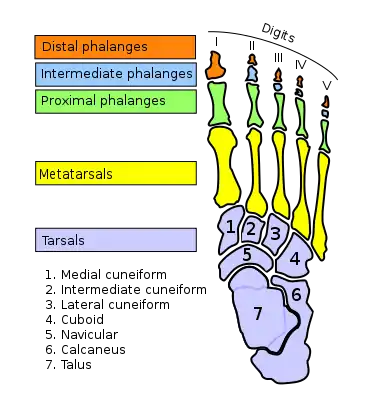

The compressive forces applied to the foot are distributed along five rays, three medial (side of big toe) and two lateral (side of little toe). The lateral rays stretch over the cuboid bone to the heel bone and the medial rays over the three cuneiform bones and the navicular bone to the ankle bone. Because the ankle bone is placed over the heel bone, these rays are adjacent near the toes but overriding near the heel, and together they form the arches of the foot that are optimized to distributed compressive forces across an uneven terrain. In this context the heel thus forms the posterior point of support that together with the balls of the large and little toes bear the brunt of the loads.[3]